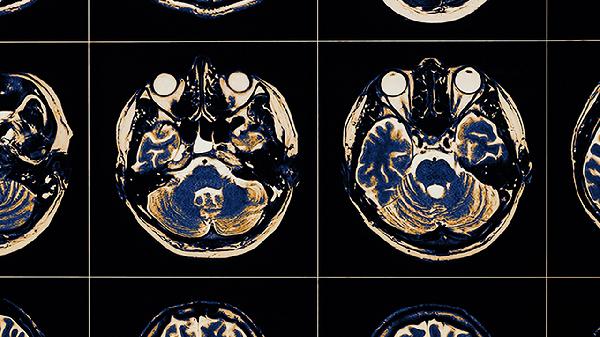

2、影像学检查

常规拍摄口腔全景片评估全口牙槽骨情况,采用锥形束CT获取三维影像数据,精确测量拟种植区的骨量、骨密度及重要解剖结构位置。对于上颌后牙区需明确上颌窦底位置,下颌后牙区需识别下颌神经管走向,避免手术损伤重要神经血管。